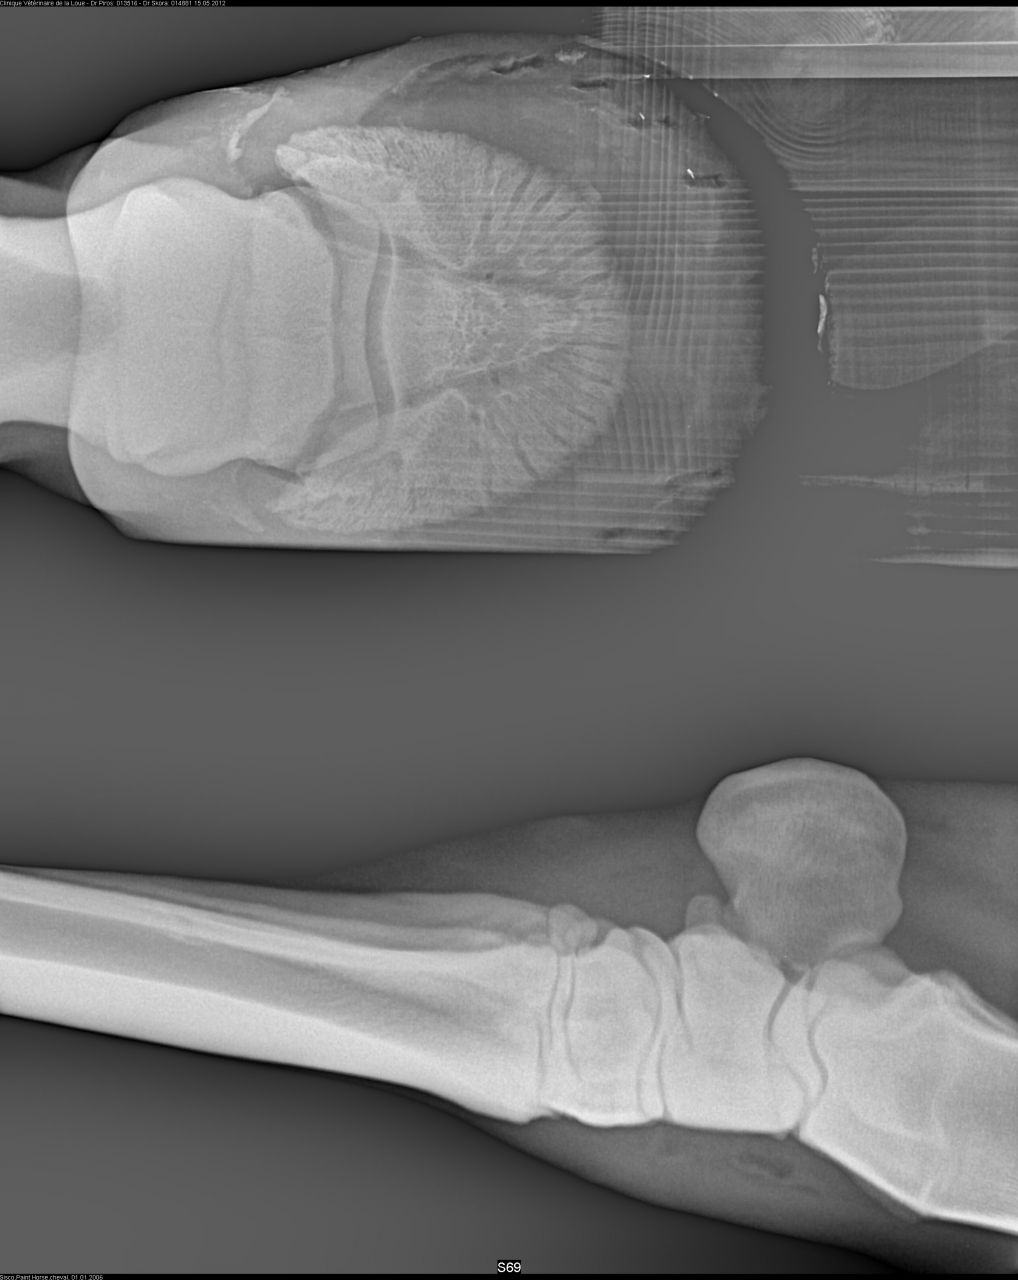

| Dire merci | Voici les premières radios de mon cheval de sa maladie antérieur droit ![]() ![]() |

| Dire merci | premieres radios antérieurs gauche![]() ![]() ![]() |

| Dire merci | les premières radios sont de juillet 2012 Voici les radios de l'antérieur droit fin septembre 2012 ![]() et celles de l'antérieur gauche ![]() ![]() |

Déconnecté | ben oui en voyant les radios, je me suis dit ostéïte direct. d'ailleurs elles sont assez impressionnantes. l'ostéïte a un caractère assez definitif,l'os ne peux pas se reminéraliser. les anti inflammatoires, c'est pour eviter qu'il y a ai une nouvelle infection qui déminéralise encore plus. quant à le remonter ....vu tes radios ... il faut imaginer que ses phalanges sont devenues aussi légère que de la roche volcanique pleine de trous ... au moindre choc, il va souffrir, et il risque des fissures de fatigue et de traumatisme aussi ... franchement, tes radios sont pas très encourageantes :S |